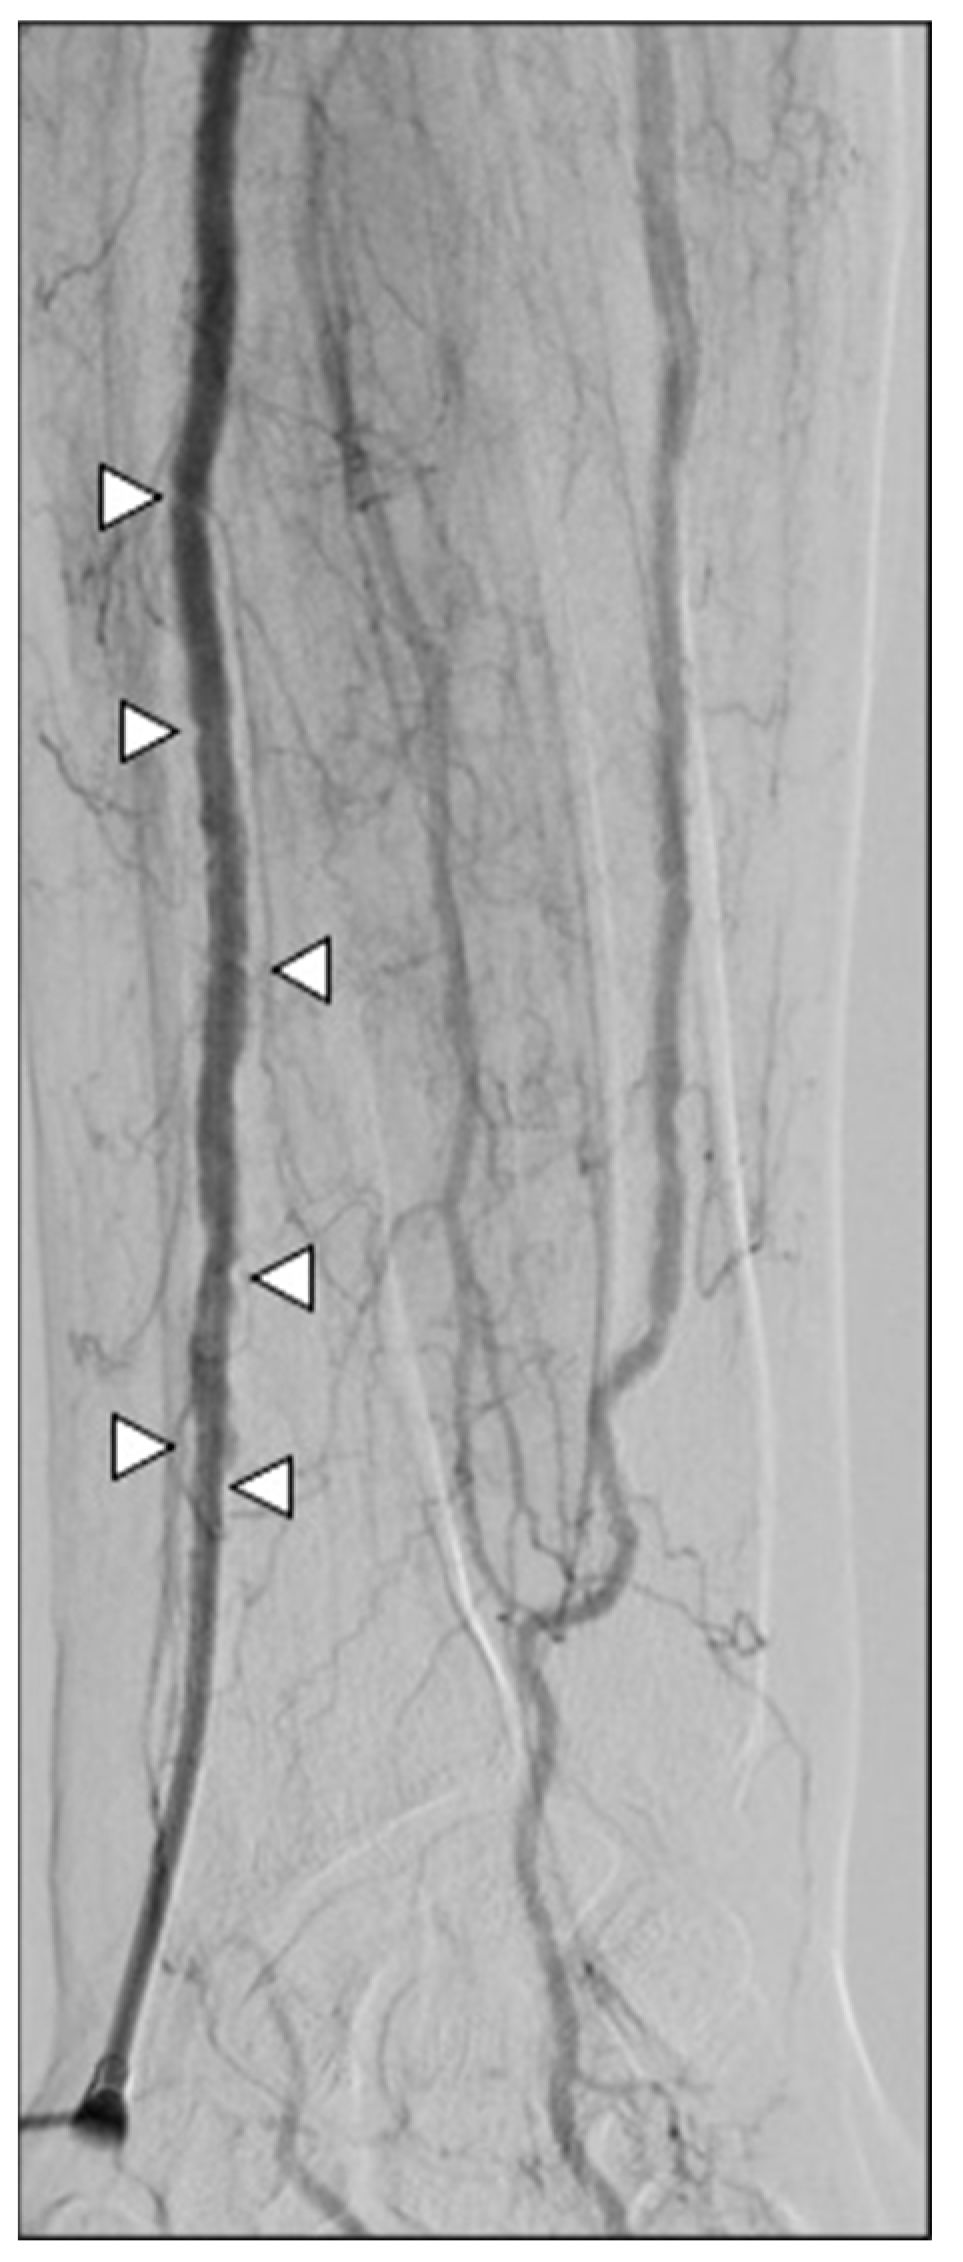

2.4. Procedures

4. Discussion